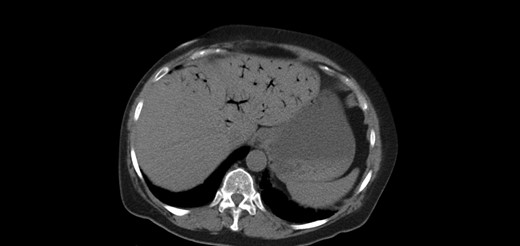

A 64-year-old female presented to the emergency department with a chief complaint of epigastric pain and nausea lasting 24 h. Relevant medical history includes congestive heart failure, interstitial lung disease, chronic obstructive pulmonary disease and prior open cholecystectomy. Home medications included a course of methylprednisolone for acute exacerbation of lung disease. On exam, her abdomen was tender and distended. Labs showed leukocytosis with normal lactate level. Figures 1 and 2 show abdominal computed tomography (CT) without contrast, significant for small bowel obstruction with intramural small bowel pneumatosis and extensive portal venous gas (PVG) within the left hepatic lobe. Emergent laparotomy was performed for acute abdomen. Exploration of the abdominal viscera revealed no evidence of inflammation, necrosis or perforation. The patient continued to have pain after surgery. Upper endoscopy was performed, revealing a non-perforated gastric ulcer which was treated with medical management until the pain resolved.

Extensive portal venous gas noted in the left lobe of the liver during the first admission. Laparotomy was negative for bowel ischemia.